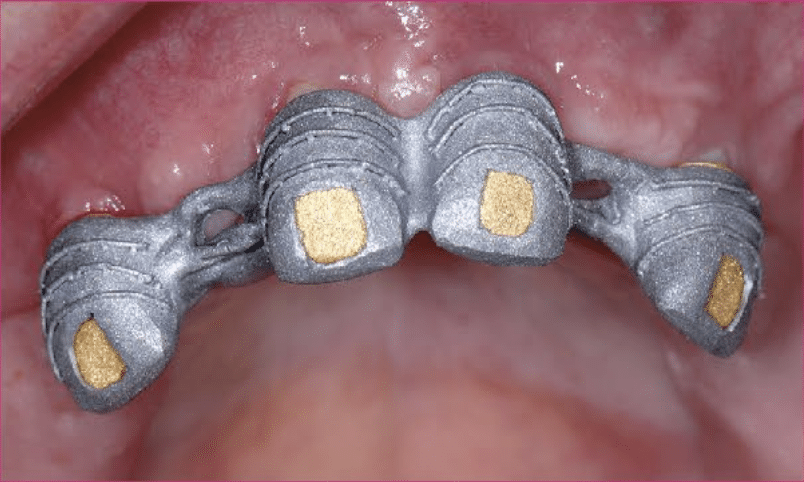

Nach dem Import der STL-Daten in die CAD-Software (3Shape, Implantstudio) wurden die Abutments konstruiert. Da die Abutments zugleich die Funktion der Primärkronen einnehmen, ist auf ein entsprechendes Design geachtet worden. Aus Zirkonoxid gefräst sowie finalisiert wurden die Kronen im Partnerlabor CS-Zahntechnik. Danach erfolgte das Verkleben mit der Titanbasis, ein sensibler Vorgang. Insbesondere das Beseitigen der Kleberrückstände im basalen Bereich sollte unter dem Mikroskop erfolgen. Die Anschlussgeometrie des Abutments bleibt unangetastet. Weiterer Schlüssel für den Erfolg einer implantatprothetischen Restauration ist ein exaktes Modell und somit die präzise Umsetzung der digitalen Daten in ein physisches Modell. Das Modell wurde im Fertigungszentrum (iTero, Align) gefräst. Die CNC-gefertigten Implantatmodelle sind hochpräzise und haben sich im digitalen implantatprothetischen Workflow der Autoren zu einem festen Bestandteil etabliert. Zum Einsatz kommen speziell entwickelte Modellanaloge, die nachträglich in die hochpräzise Bohrung eingebracht werden.

2. Sekundär- und Tertiärstruktur

Voraussetzung für die dauerhaft gute Funktion von Doppelkronen ist die exzellente Passung der beiden „Partner“ (Zirkonoxid-Kappe und Galvano-Kappe) (Abb. 5b). Die hochglatten Flächen der Zirkonoxid-Kappen bildeten die Basis für den Galvanisierungsprozess. Im digitalen Workflow bleibend, wurde das Tertiärgerüst im Laser-Melting-Verfahren hergestellt und intraoral die Galvano-Kappen im Gerüst verklebt. Die Passivierung im Mund gilt als Voraussetzung für die langzeitstabile Funktion der teleskopierenden Brücke. Nach erneuter Bissnahme und Kieferrelationsbestimmung sowie einer Ästhetikeinprobe konnte die Restauration fertiggestellt und in der Praxis eingegliedert werden (Abb. 6-12). Großer Vorteil des beschriebenen digitalgestützten Vorgehens: Der Patient musste zu keiner Zeit mit einer Silikonabformung „belastet“ werden. Bis auf die ästhetisch-funktionelle Umsetzung konnte komplett im digitalen Workflow gearbeitet werden.